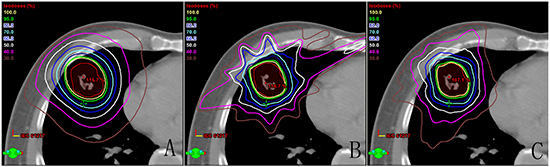

One example of dose distribution was shown in Figure 1 for each treatment technique. Dose volume histogram (DVH) was created for each treatment plan and utilized to assess the PTV coverage and dose to OARs. All DCA, IMRT and RA plans met the RTOG 0915 protocol criteria for the PTV coverage.

Figure 1: Comparison of dose distribution for each of the three techniques: A. dynamic conformal arc therapy, B. intensity modulated radiation therapy, C. double partial arcs Rapidarc.